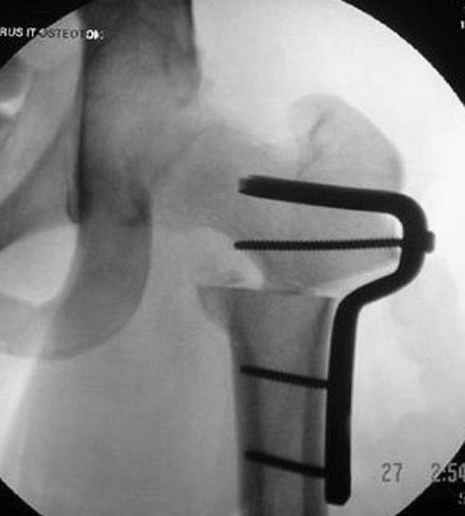

Несколько снимков из моей коллекции, чтобы разьяснить, почему мы до сих пор делаем различные варианты остеотомии.

На рисунке N1 предоперационный план лечения ложного сустава шейки бедра- линия ложного сустава, угол и направление введения импланта, клиновидная остеотомия в градусах и миллиметрах, второй снимок после коррекции, расчет, на сколько удлиняется конечность и размеры импланта;

N3 рисунок окончательный снимок, после операции моя рентгенограмма должен выглядеть примерно как эта картина. На N4 снимке клин перед удалением; N5 послеоперации 3 нед.; N6 окончательная рентгенограмма.

пластическая модель; и коррекция бедра аппаратом Илизарова.

Почему не замена гвоздя с рассверливанием, а аппарат?

хотя даже если бы и инфекция , то nail exchange с рассверливанием канала - вариант дебрайдмента) Я думаю, что последовательность развития событий:

Узкий к-м канал - тонкий гвоздь- усталостный перелом дистальных винтов - развитие нестабильности и как ее результат остеолиз вокруг гвоздя - деформация анатомической оси бедра. Похоже, что я понял почему аппарат, а не новый гвоздь:-)